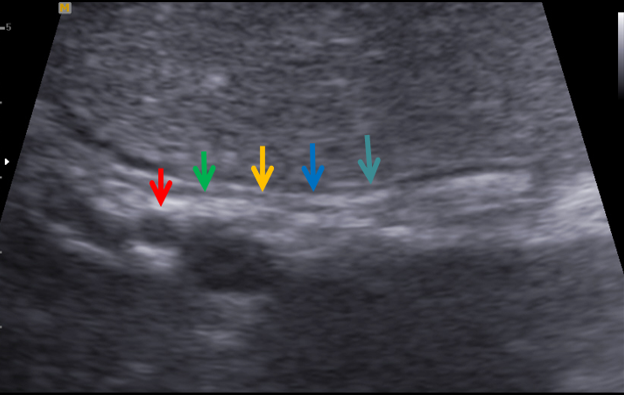

胃壁三强二弱结构(胃小弯)